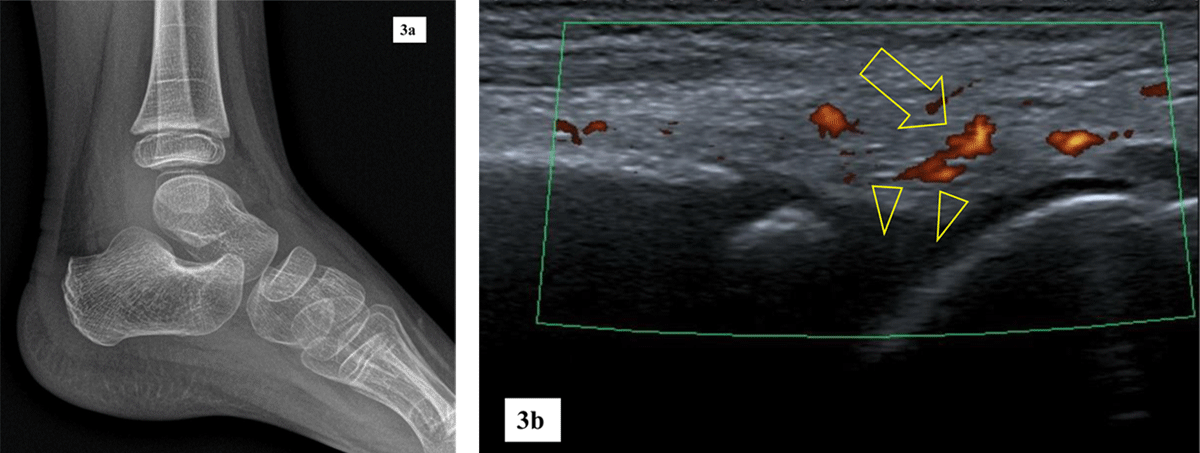

Figure 3

5-year-old girl with confirmed JIA.

a. Lateral radiograph of a left ankle is unremarkable.

b. Sagittal ultrasound of the left ankle shows hypervascular synovium on Power Doppler mode (arrow) and small tibiotalar effusion (arrowheads).